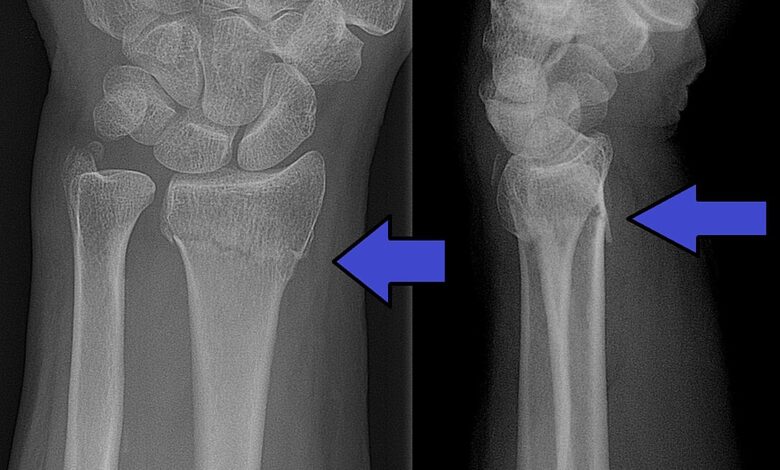

ابتكار كوري لإصلاح كسور العظام في دقائق يطلق مضادات حيوية تلقائيا

نشر مركز المعلومات ودعم اتخاذ القرار بمجلس الوزراء مقطع فيديو عبر صفحته الرسمية. يكشف عن تقنية طبية جديدة من كوريا الجنوبية. قادرة على إصلاح كسور العظام خلال دقائق مع إطلاق مضادات حيوية بشكل تلقائي للوقاية من العدوى،